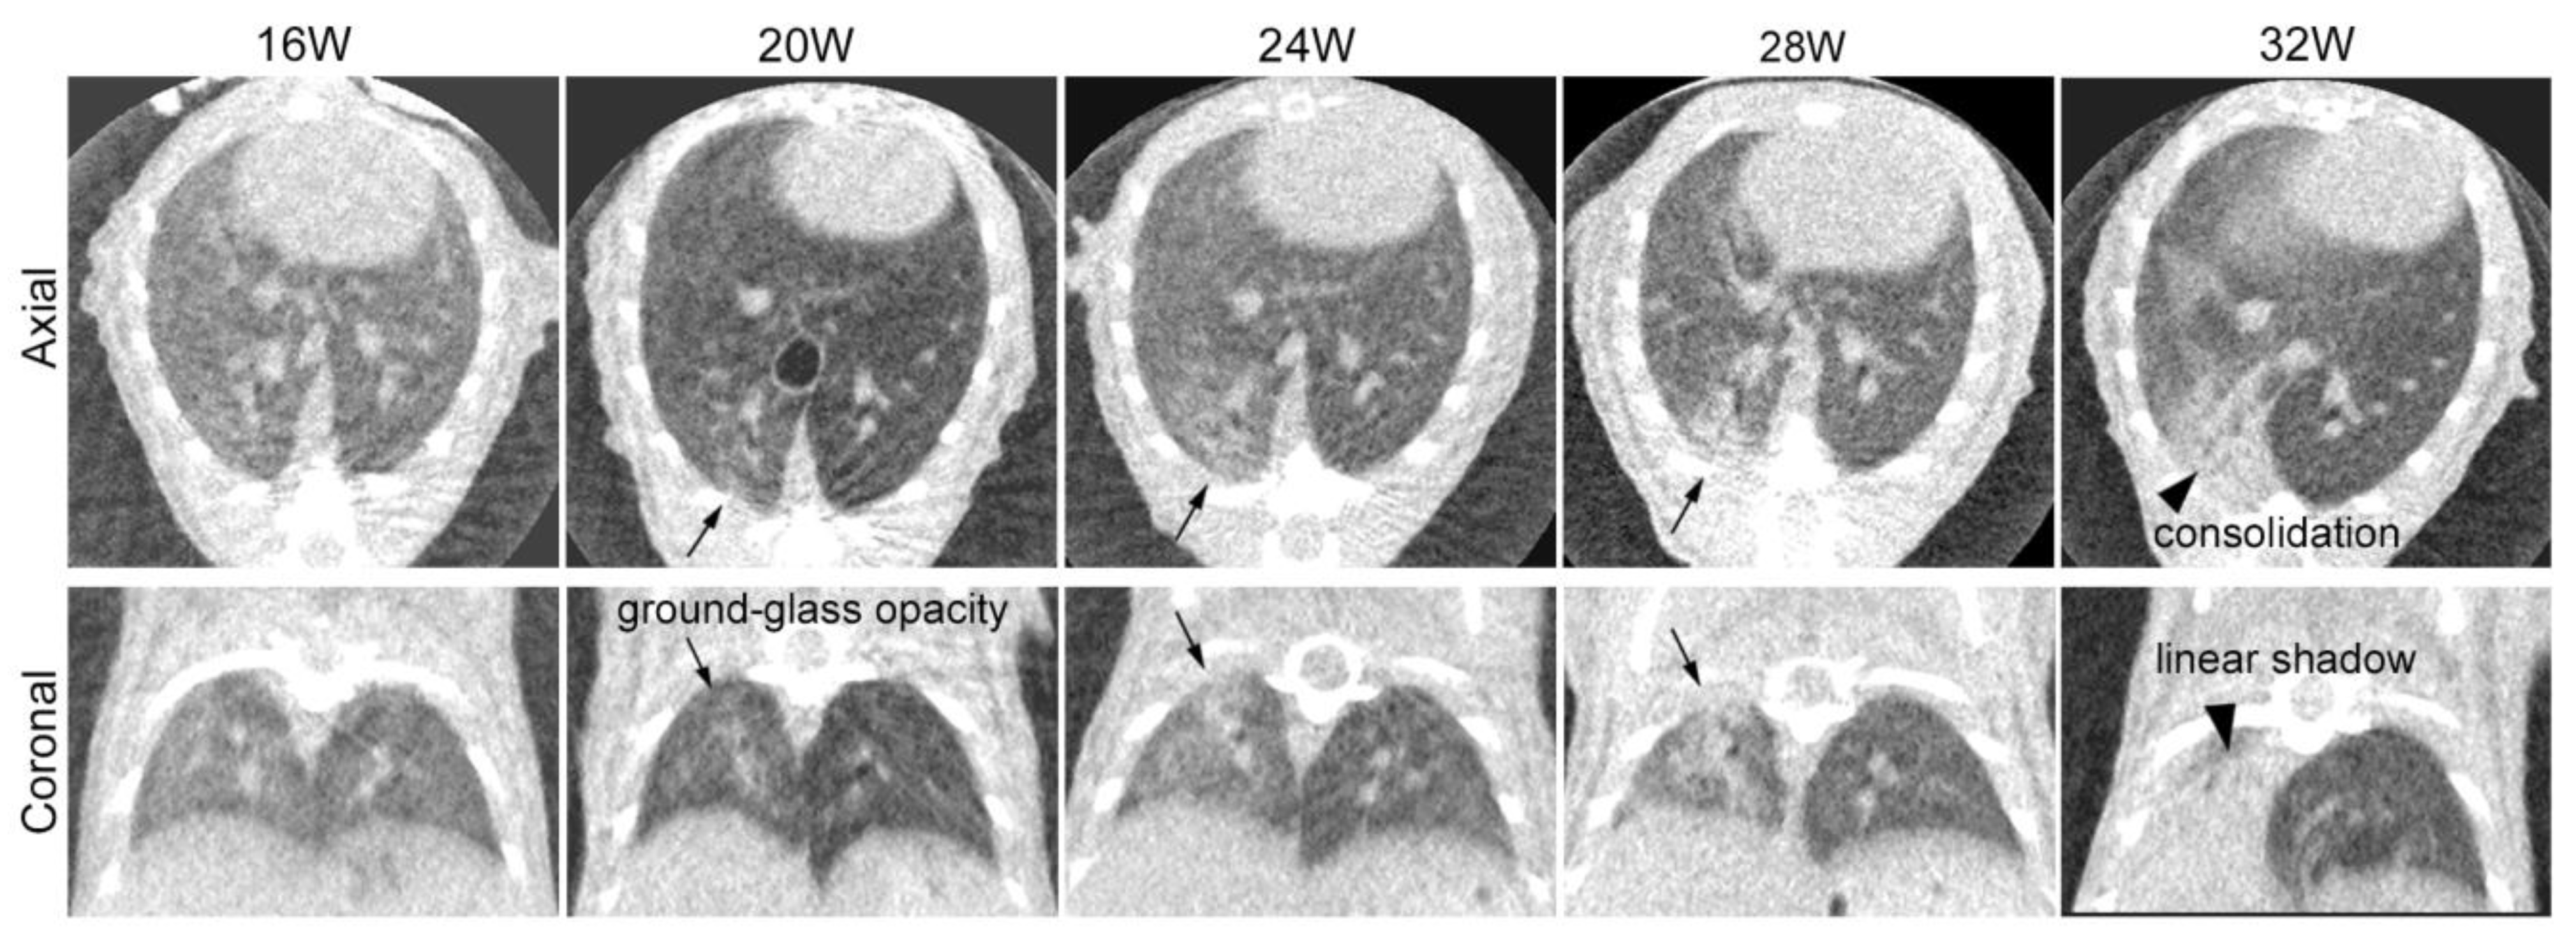

Sequential CT scans were obtained for the same three mice to follow up on the time-dependent CT changes in the lung (Figure 2). The images were reconstructed by obtaining end-expiratory images using a respiratory gating technique. At 20 weeks after irradiation, one mouse died shortly after inhalation anesthesia for a CT scan. Respiratory and circulatory failure due to oversedation and hypothermia were considered possible causes of death. The other mouse was followed until 32 weeks after irradiation. We could not observe any obvious changes in the mice until 16 weeks after irradiation. At 20 weeks, we observed patchy ground-glass opacity in the irradiated right lung. By 24 and 28 weeks, this opacity had expanded and become denser. At 32 weeks, we noted linear shadows, consolidation with lung volume loss, and compensated expansion in the non-irradiated left lung.

4.2. Sequential Changes in CT Images after Irradiation

We obtained sequential CT scans for the same individual in Group 1 from 12 weeks up to 32 weeks after irradiation. At 20 weeks after irradiation, patchy ground-glass opacity appeared. Subsequently, the ground-glass-like lesion gradually expanded and progressed to consolidation at around 24 to 28 weeks, followed by the development of atelectasis at 32 weeks. These time-dependent changes in the CT imaging were also confirmed by the Group 2 experiments, and the images were similar to those after SBRT for human lungs [1,35,36]. Previous mouse experiments have reported a similar sequential change in the CT findings of RP/RF. However, they appeared slightly earlier [2,5,6,7,33], possibly due to differences in the mouse strain, the irradiation field, and the irradiation dose used in the experiments.

Figure 2. Sequential computed tomography (CT) axial and coronal images of a mouse after partial right lung irradiation at 30 Gy/1fr: CT scans were sequentially obtained for the same mice to confirm the time-dependent changes in the irradiated lung. We found no change until 16 weeks after irradiation. Findings of radiation pneumonia (ground-glass opacity and pulmonary infiltrate) were observed in the right lung 20 weeks after irradiation (arrow) and expanded until 28 weeks after irradiation. At 32 weeks after irradiation, findings of radiation fibrosis (consolidation with volume loss) were observed (arrowhead).